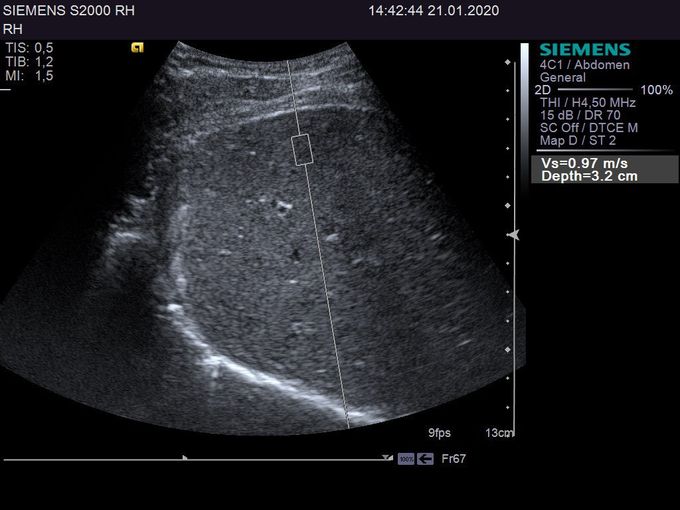

Кроме новой техники, можно заказать восстановленные медицинские системы: ультразвуковые сканеры, томографы, флюороскопы, ангиографы и хирургические установки С-дуга.